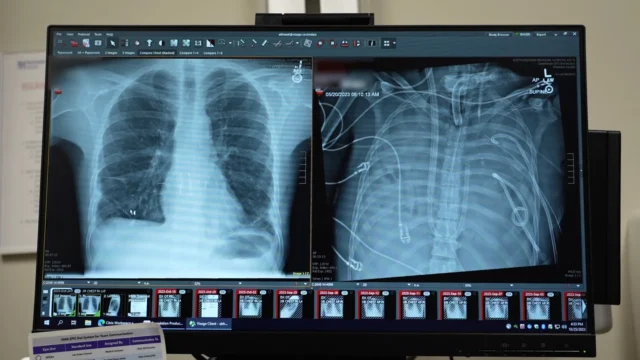

Em reportagem publicada na revista Cell Press eos cirurgiões detalharam como removeram o pulmão gravemente infectado de um homem e usaram um sistema de “pulmão artificial” para mantê-lo vivo até que um transplante duplo de pulmão pudesse ser realizado. O caso destaca uma nova maneira potencial de manter vivos pacientes gravemente enfermos enquanto esperam por órgãos doados.

O paciente, um homem de 33 anos, sofria de síndrome do desconforto respiratório agudo (SDRA), uma doença perigosa em que inflamação e infecção inundam os pulmões. Sua doença começou com gripe e piorou rapidamente para pneumonia bacteriana. À medida que sua condição piorou, seus pulmões, coração e rins começaram a falhar. Nesse ponto, um transplante duplo de pulmão tornou-se sua única chance de sobrevivência.

Os pulmões do homem não podiam ser salvos e promoviam ativamente a propagação da infecção. No entanto, ele estava instável demais para um transplante imediato, então os médicos precisaram de tempo para estabilizar sua condição.

Para resolver este problema, a equipe médica desenvolveu um sistema pulmonar artificial projetado para substituir temporariamente o papel dos pulmões. Este sistema oxigena o sangue, remove o dióxido de carbono e apoia a circulação para que o coração e outros órgãos possam continuar a funcionar mesmo que o paciente não tenha pulmões.

Após a remoção do pulmão danificado, a condição do paciente começou a melhorar. Sua pressão arterial se estabilizou, seus órgãos começaram a se recuperar e suas infecções estavam sob controle. Dois dias depois, os pulmões dos doadores ficaram disponíveis e os cirurgiões realizaram com sucesso um transplante duplo de pulmão. Mais de dois anos depois, o paciente vive uma vida normal com função pulmonar saudável.